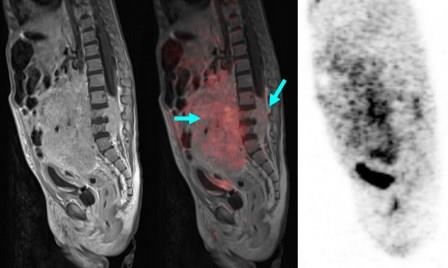

Weniger Strahlen dank PET-MRT

Seit 2011 steht der Leipziger Kinderradiologie auch ein PET-MRT im Methodenportefeuille zur Verfügung, das im Leipziger PET-MRT-Konsortium gemeinsam von der Nuklearmedizin, der Diagnostischen Radiologie, der Neuroradiologie und der Kinderradiologie betrieben wird.

Erste eigene Erfahrungen mit dieser Hybridbildgebung zeigen, dass im Vergleich mit der zuvor angewendeten PET-CT-Technik bei Kindern eine enorme Reduktion der Strahlenexposition von rund 80 % erreicht werden kann, ohne dass die diagnostische Sicherheit darunter leidet. Die PET-MRT wird daher in Leipzig - bei klinischer Indikation - bei allen Patienten mit dissiminierenden onkologischen Erkrankungen im Kindesalter eingesetzt. Die ersten Leipziger Erfahrungen mit der Methode wurden im Januar 2013 in der Zeitschrift Pediatric Radiology publiziert. Im Methodenwettbewerb scheint sich für das PET-MRT hier eine klare Indikation herauszukristallisieren (Kinder-PET-MR). Dass diese Einschätzung auch von anderen Kinderzentren geteilt wird, dafür spricht auch das weltweit große Interesse von kinderonkologischen Einrichtungen an dieser neuen Hybrid-Bildgebungsmodalität.